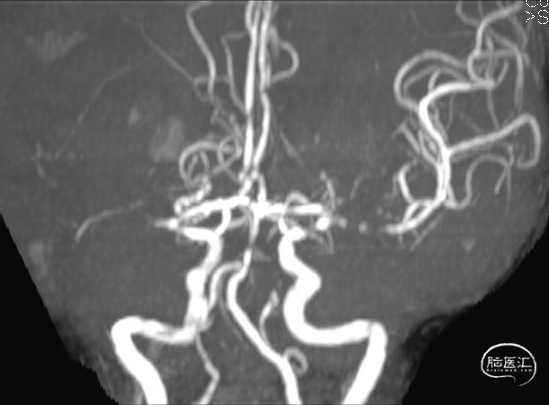

MRA